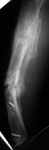

This is a 45 year old gentleman who 8 years ago sustained a midshaft tibia fracture originally treated with plate and screws which became infected. The plate and screws were removed, dead bone was resected and Ilizarov was placed with proximal corticotomy and transport into distal defect. Multiple complications during this including refracture and infection.

He now shows up in my clinic with pain and deformity as seen in the images. He has a draining sinus which drains on and off intermittently. He really wants to save his leg but i think an amputation will serve him best. He has a rigid ankle and midfoot. Currently his ankle is fixed in about 10 degrees of dorsiflexion. He ambulates with crutches because of his pain. He has sensation distally with good capillary refill, no palpable pulse. Angiogram shows all 3 vessels present in leg.